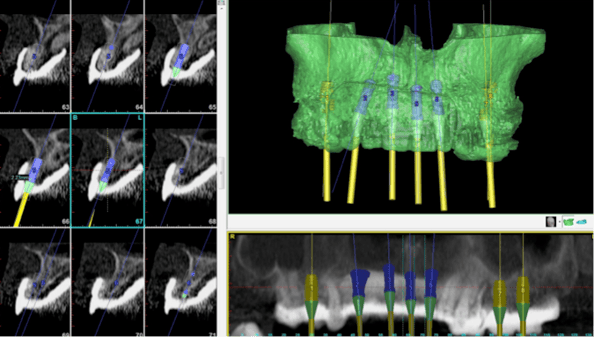

One of the challenges to a full mouth dental implant-supported prostheis is the transition from a partially dentate state to a fully edentulous state. Many patients are unable to manage a complete denture, especially for the lower jaw. To avoid the inconvenience of having to adapt to a set of full dentures in the interim period, we decided to go with immediate loading of the implants with a fixed temporary prosthesis. This was done using CT-guided dental implant surgery. First, a radio-opaque scan prostheses were made and CT scans were taken and the data were entered into Simplant Planner, a dental implant treatment planning software. Based on the ideal setup of teeth in the scan prostheses, implants were placed in the model generated in the software. The plan was uploaded to the Simplant facility in Belgium.

Based on the plan, a surgical guide was made by stereolithography. The purpose of the guide was to ensure that the implants would be placed in exactly the positions as planned. The guides were then couriered back to a Singapore laboratory for fabrication of provisional prostheses that would be fitted onto the implant on the day of implant surgery. On the day of surgery, the guides were fitted over the existing teeth and implants placed in accordance to the guide. Once the implants were inserted, all the remaining teeth were extracted and the prostheses fitted onto the implants.